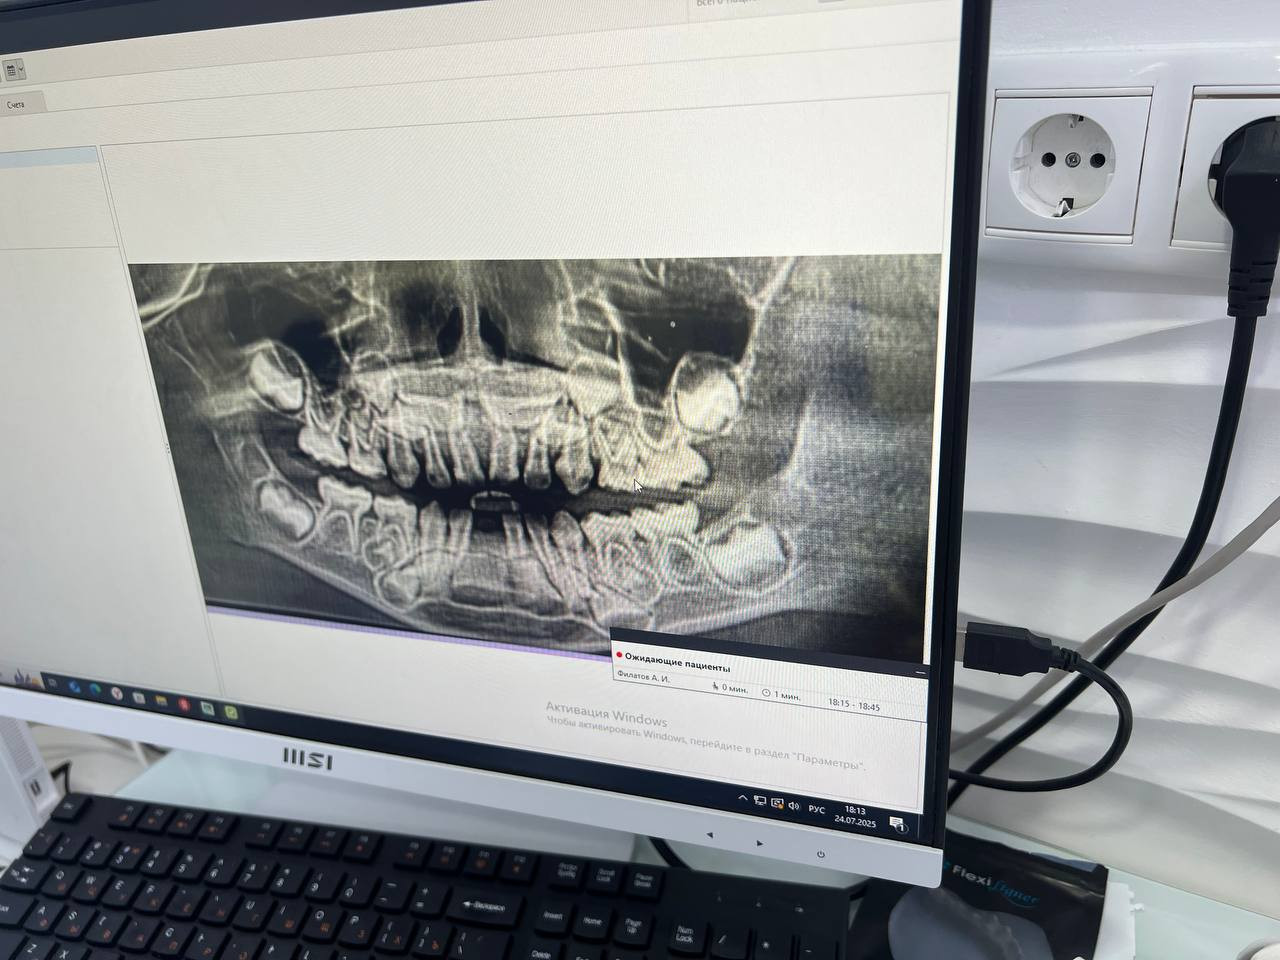

Добрый день. У ребенка в три года выпал зуб, были сделано кт, результаты ниже. По кт видно недостаточность костной ткани. Других проблем у ребенка нет. Щелочная фосфатаза, кальций, фосфор, будет сдан на днях. Какие ещё анализы можно сдать и может ли это быть вариантом нормы?

Здравствуйте. По КТ действительно видно, что костная ткань в зоне зубов тонкая, но в 3 года это может быть вариантом нормы, особенно если травмы не было и ребёнок развивается без отклонений.

Здравствуйте. В этом возрасте костная ткань ещё формируется и умеренная недостаточность на КТ может быть физиологической, особенно если зуб выпал без травмы и общее состояние ребёнка хорошее. Помимо щелочной фосфатазы, кальция и фосфора желательно сдать: